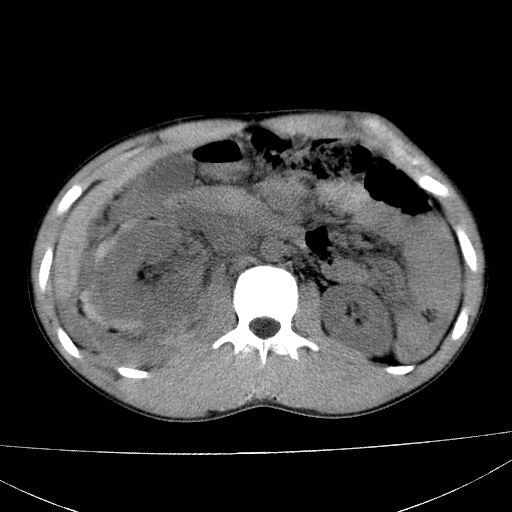

标题: CT15860:男,21岁,腹部外伤2小时伴胸疼。 [打印本页]

标题: CT15860:男,21岁,腹部外伤2小时伴胸疼。

b超示:肝破裂。

肝脏及肾脏明显有损伤性改变并激发腹腔内积液(血),以肝脏撕裂及肾周积血显著。

1)肝破裂伴腹腔积液(血)。2)右肾破裂伴右肾包膜下及肾周血肿。3)腹部空腔脏器穿孔可能。4)右侧少量胸腔积液(血)。

1)肝破裂伴腹腔积液(血)。2)右肾破裂伴右肾包膜下及肾周血肿。3)右侧少量胸腔积液(血)。

肝、右肾包膜下血肿,右侧腰大肌及腹膜后血肿;腹腔少量积血;腹腔疑有少量游离气体伴肠破裂。

1肝挫伤伴腹腔积液。2右肾挫裂伤伴右肾包膜及肾后间隙肿血肿。3右肾脏周围的积气,十二指肠显示结构不清,考虑十二指肠降部破裂可能性大。